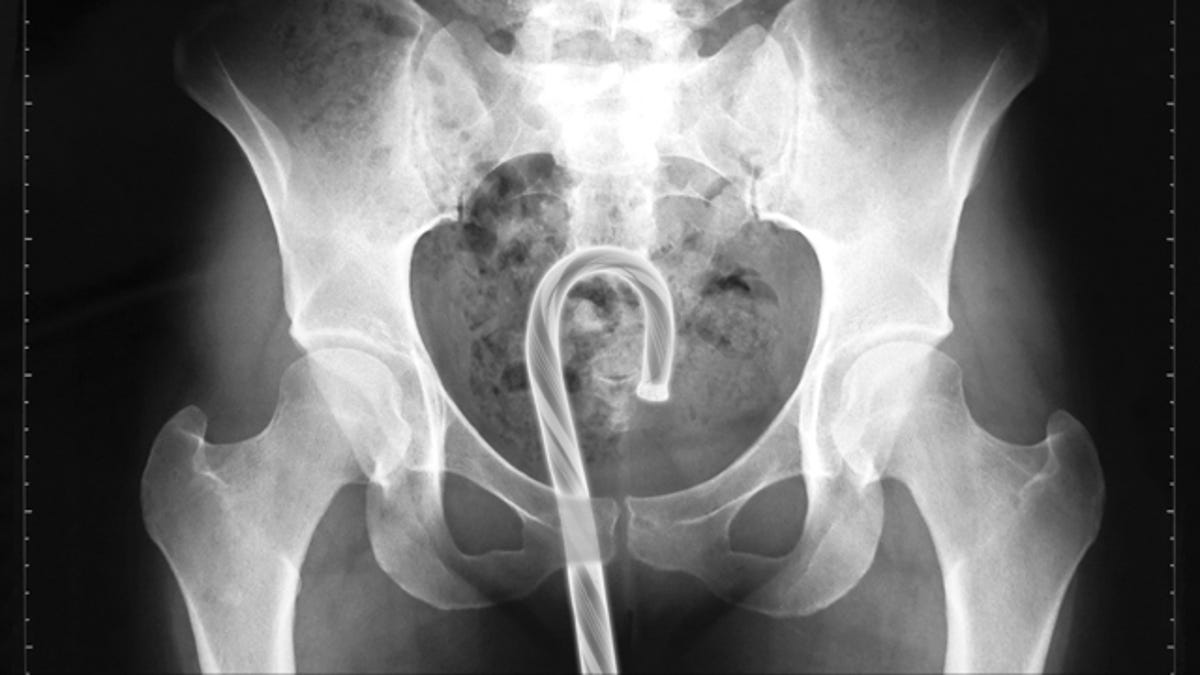

As in past years, the U.S. Consumer Product Safety Commission has created a searchable database of emergency room visits around the country. And as in past years, we have trolled the data for the finest examples of insertions showcasing extraordinarily bad luck and/or ingenuity. [Note: Headline has been updated. These…